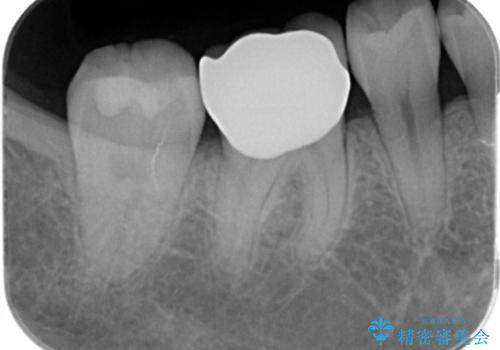

古い樹脂と虫歯を拡大鏡下でしっかり取り除き、ジルコニアクラウンにて治療しました。

ジルコニアクラウンは劣化しにくく虫歯の再発のリスクが低いです。